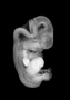

Carnegie Stage 20 (50 post-ovulatory days)

Most embryos at stage 20 are approximately 50-51 postovulatory days old and measure 21-23 mm in length. Distinguishing criteria for this stage include upper limbs slightly bent at the elbows, short stubby fingers, hands curving over the cardiac region but still far apart from each other, and a fringe-like vascular plexus that marks growth centers laterally in the superficial tissues of the head.

Although some of the photographs below show abnormal embryos, the animations and MRI slice images all depict normal embryos. Abnormal embryos are noted in the titles of the large photos when they are opened.